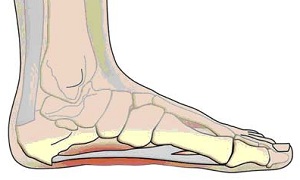

Підошовний апоневроз - це підошовна фасція, що з'єднує п'ятковий бугор і головки плеснових кісток, в результаті чого людині забезпечується підтримка поздовжнього зводу стопи.

Оскільки на п'яту припадає все навантаження під час ходьби, тут відзначається розвиток п'яткової шпори - кісткового наросту на п'ятковому горбі, спровокованого запаленням апоневроза.